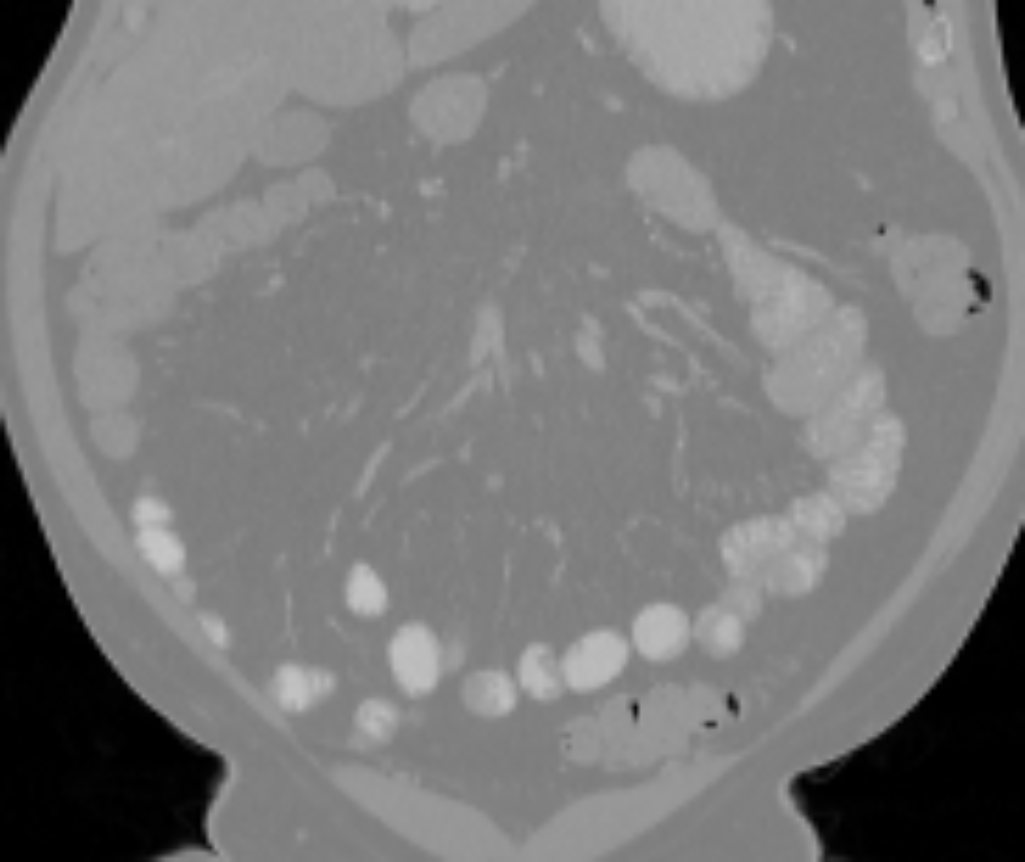

The small bowel has a cylindrical shape but also has many touchings with different parts along its path, which makes it have variable topologies across patients and time. It is inappropriate to apply a constant topological constraint to such organs. Fig. 1 shows an example of the small bowel path covered by the lumpy ground-truth (GT) segmentation.

GT labels were achieved by an experienced radiologist using 3DSlicer111https://www.slicer.org [6] based on the following steps. Firstly, the path of the small bowel is drawn as interpolated curves which connect a series of manually placed points inside the small bowel. Secondly, we grow the curves using a margin of and threshold it again using a Hounsfield unit (HU) range of . Manually drawn air pockets, which have much lower HU values, are also added during the second step. Produced errors are manually fixed in the final step. We note that this annotation procedure took one or two full days for each volume. Finally, the dataset includes the two types of labels, which are the path and segmentation of the small bowel as shown in Fig. 1.